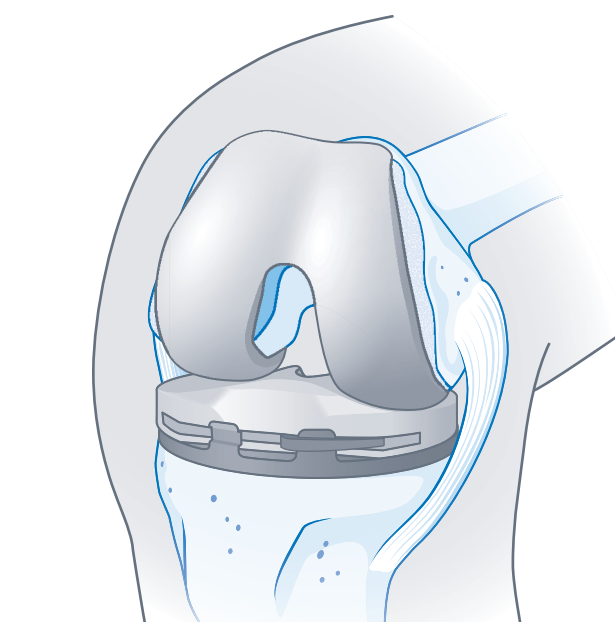

Oberflächenersatz

Ein Oberflächenersatz kommt infrage, wenn mehrere Gelenkabschnitte (innerer und äußerer Anteil) betroffen sind; bei zusätzlicher Schädigung des kniescheibenseitigen Gelenkabschnitts wird dieser ggf. mitersetzt.